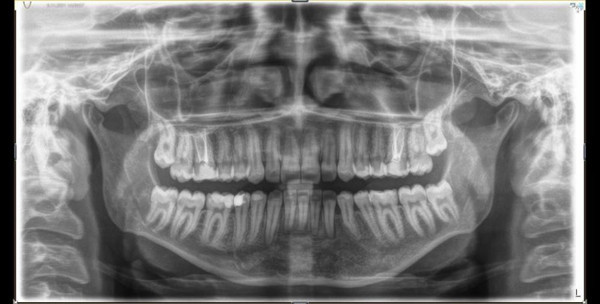

Abone olEskişehir’de yaşayan 18 yaşındaki Tuğçe Tüfek, yıllar önce dolgu yaptırmak için gittiği bir hastanede çene bölgesinde kist olduğunu öğrendi. Başvurduğu birçok hastanede kistin doğuştan var olduğu ve tedavisinin yapılamayacağını söylenerek geri çevrildi. Eskişehir Osmangazi Üniversitesi Diş Hekimliği Fakültesi’ne gelen Tuğçe Tüfek, ilk kez olumlu dönüş alınca tedavi sürecine başladı. Çene bölgesinde sağdan sola uzanan 7,5 santimetrelik kist için iki aşamalı başlatılan tedavide ilk önce küçültme operasyonu yapıldı. Uzun soluklu takip ve kontrollerin ardından tedavinin üçüncü yılında küçülen kistin alınması için bıçak altına yatan Tuğçe Tüfek, başarılı bir operasyonla sağlığına kavuştu.

Gömülü bir dişle birlikte 7,5 santimetrelik kistin çene bölgesindeki sinirleri ve kemik yapısını etkilediğini belirten ESOGÜ Ağız, Diş ve Çene Cerrahisi Anabilim Dalı Öğretim Üyesi Doç. Dr. Nesrin Saruhan, hazırlıksız yapılacak ameliyatın büyük risk taşıdığını belirtti. Sinirlerde uyuşukluk ve çene kemiğinde kırık oluşmasını engellemek için kist küçültme ameliyatı yaptıklarını belirten Doç. Dr. Nesrin Saruhan, “Tuğçe bize geldiğinde 15 yaşındaydı. Alt çenesinde sağdan sola uzanan 7,5 santimetrelik oldukça büyük bir kisti vardı. Bununla ilgili birkaç merkeze gitmiş ama Eskişehir’de bu tedavinin yapılamayacağı bilgisi verilmiş. Kendisi kliniğimize geldiğinde önce radyolojik muayenelerimizi yaptık. Oldukça büyük bir kist vardı. Hem sinirle ilişkiliydi hem de alt çene kemiğini zayıflatmıştı. Bir de gömülü dişi vardı. İlk etapta parça alıp biyopsisini yaptık. Kist tanısını koyduktan sonra iki aşamalı tedavi planladık. Çünkü mevcut 7,5 santimetrelik kistle ameliyat yapsaydık hem sinirlerde uyuşukluk kalacaktı hem çene kemiğinde kırılma riski oluşacaktı hem de yaklaşık 10 tane dişini kaybetme riski ortaya çıkacaktı. Hastamızın yaşı da küçüktü” dedi.

Yapılan iki aşamalı tedaviyle kisti, küçülttükten sonra ameliyata hazır hale getirdiklerini belirten Doç. Dr. Nesrin Saruhan, uzun hazırlık sürecinin riskleri ortadan kaldırdığını söyledi. Bu tarz durumlarda hastaların korkmadan biran önce tedavi için başvurması gerektiğini belirten Saruhan, “İlk etapta kisti küçültme ameliyatı yaptık. Ayda bir kontrollere geldi. Var olan 7,5 santimetrelik kisti oldukça küçük hale getirdik. Böylece kisti hem sinirden uzaklaştırdık hem de alt çenede yeni kemik oluşumunu bekledik. Sonrasında ise genel anestezi ile ameliyatı yaptık. Hem kisti çıkarttık hem de kiste neden olan gömülü dişi çıkarttık. Geri kalan dişlerinde de kayıp yaşamadık. Sinirle alakalı bir sorun da oluşmadı. Uyuşukluğu olmadan dişler ağızdaki yerinde bulunuyordu. En önemlisi de alt çenede hiçbir kırık olmadı ve kendiliğinden kemik oluşumu sağlandı. Kist küçültme tedavileri zaman alabiliyor ama sonuçta hasta daha başarılı bir yöntemle tedavi oluyor. Hem hekim hem de hasta için oldukça iyi bir tedavi protokolü olmuş oldu. Bu tip durumlarda hastaların korkmamaları ve ilerlemesini engellemek adına mutlaka yapılması gereken oral patolojileri yaptırması gerekiyor.” dedi.